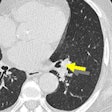

Lung-RADS category 4X helps diagnose lung cancer

April 26, 2017